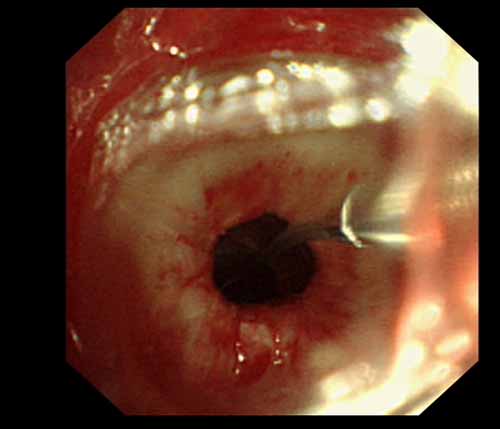

患者李某某,女,45歲,因氣管插管咳嗽、喘憋10天入院。頸部CT檢查示聲門下約20mm處氣管明顯狹窄,狹窄段長約26mm,最窄處直徑約4.4mm。支氣管鏡檢查見聲門下約2cm氣管呈漏斗狀縮窄,直徑約4-5mm,支氣管鏡無法通過。經(jīng)科室討論,決定行電子支氣管鏡下氣管球囊擴(kuò)張治療。與患者及家屬充分溝通并經(jīng)三方見證談話簽署知情同意書后,在患者持續(xù)吸氧、局麻下,科主任于世倫主任醫(yī)師帶領(lǐng)治療小組為患者實(shí)行電子支氣管鏡下氣管球囊擴(kuò)張術(shù)。手術(shù)過程順利,出血量很少,術(shù)后患者呼吸困難癥狀即可明顯緩解。10天后行二次擴(kuò)張,患者日?;顒訜o明顯喘憋,二次術(shù)后5天出院。

術(shù)前聲門下的漏斗樣狹窄口 術(shù)中球囊擴(kuò)張 術(shù)后擴(kuò)張開的氣管管腔